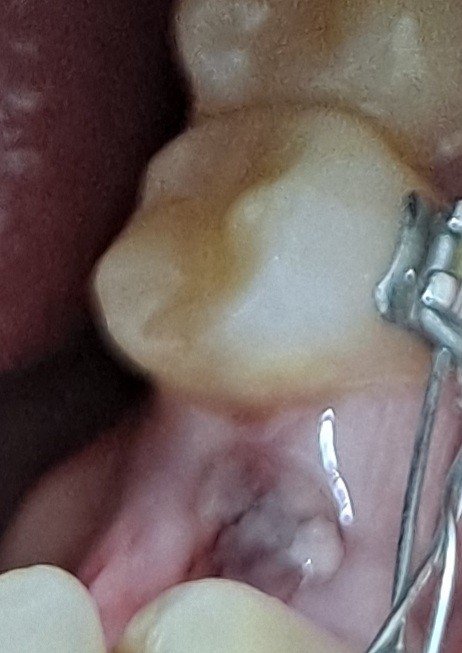

아무튼 그래서 방금 딱 봤는데 무슨 하얀색 염증 여드름처럼 생긴 막 처럼 생긴게 있는거야

원래 핏덩이같은것만 있었는데

그래서 얇은걸로 살짝 건드려보니까 먹이 아니라 덩어리같은게 박혀있더라

사진이 좀 더럽게 찍히긴 했어